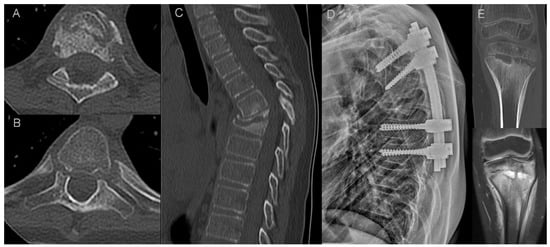

- bone marrow edema (BME) presence and pattern (Figure 1):

Figure 1. Bone marrow edema (BME) patterns appreciated on T2 FS/STIR MRI images. (A). corner inflammatory lesions (arrow); (B). propagating (arrowheads); (C). semicircular/curvilinear (dotted line); (D). diffuse—patchy (in the upper two vertebrae) and solid (in the lowest vertebra).- vertebral body corner inflammatory lesions (CIL)—active Romanus lesion defined as small foci of BME at the vertebral corners,